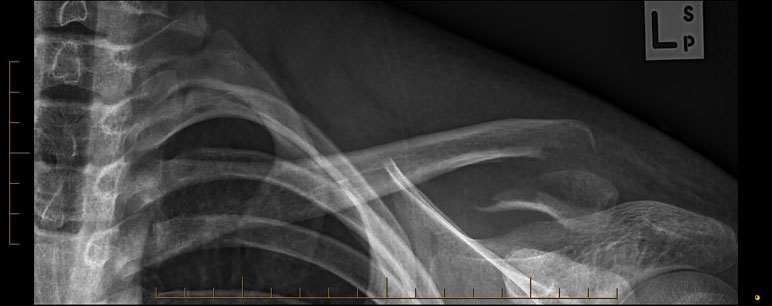

A 15 year old female fell from her pushbike causing a displaced left mid-shaft clavicular fracture. Seen 5 days later, plate & screws inserted 2 days later.

Image

DIsplaced fracture before surgery

DIsplaced fracture after surgery

Move the slider to compare before surgery and after surgery